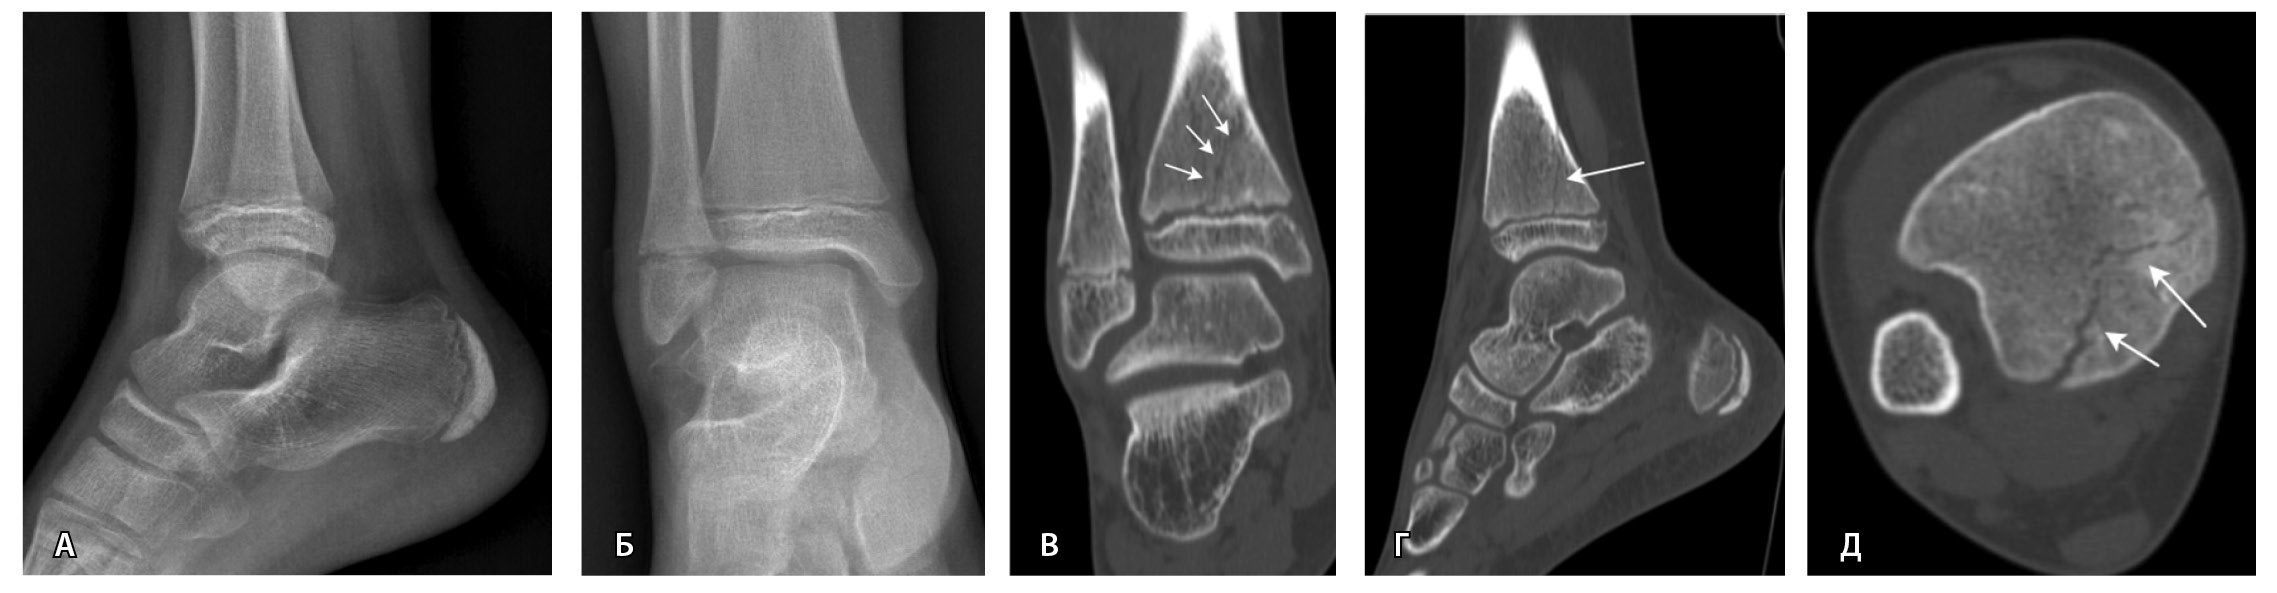

МРТ – первоначальный метод диагностики при подозрении на стрессовые переломы, так как ранним признаком таких переломов служит отек костного мозга пораженной кости, ярко выделяющийся среди остальных неизмененных костей. Отсутствие визуализации костного мозга затрудняет диагностику такого рода повреждений при рентгенографии и КТ (рис. 4). Чувствительность МРТ в выявлении стресс-переломов достигает 99% (95–100%), а специфичность – 97% (88–100%). Несмотря на то что исторически сцинтиграфия была основным методом обнаружения стресс-переломов с почти 100% чувствительностью, в настоящее время выполнение радионуклидного метода не рекомендуется из-за его низкой специфичности и высокой дозы ионизирующего излучения [54].

Рис. 4. Стресс-перелом промежуточной клиновидной кости: А – компьютерная томография (КТ), сагиттальная плоскость; Б – КТ, аксиальная плоскость; В – импульсная последовательность STIR, сагиттальная плоскость. Линия стресс-перелома слабо видна на КТ-изображениях, обнаруживается только при сагиттальных КТ-реконструкциях (стрелки). На изображениях магнитно-резонансной томографии отек костного мозга промежуточной клиновидной кости в режиме STIR ярко выделяется среди неизмененных костей